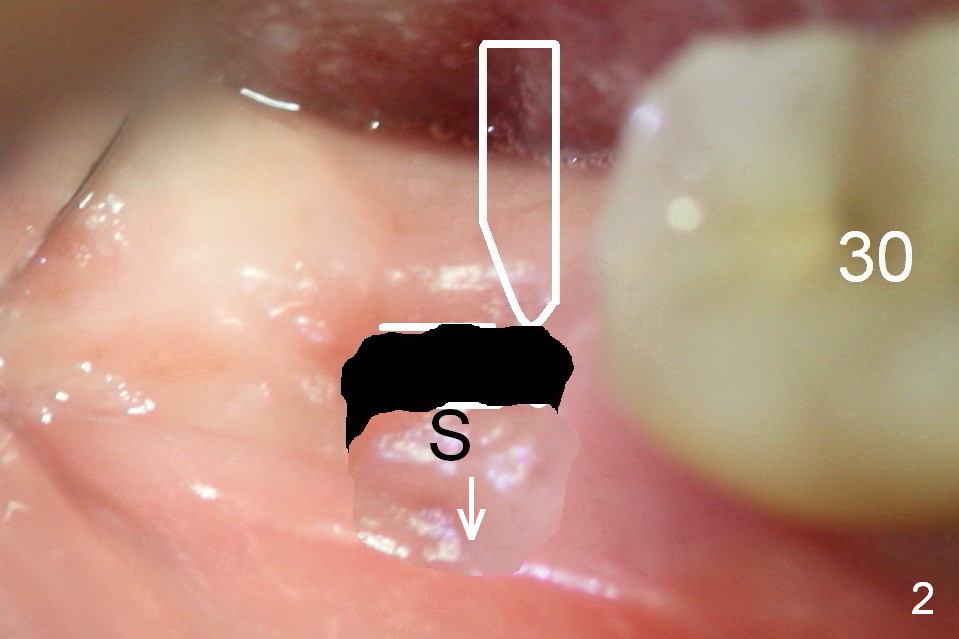

Steps of Bone Expansion (Illustration)

After incision and flap elevation, use #15 blade (Fig.1 white outline) to start bone expansion as lingual as possible (white line). Use bone scalpels, bone blades and D osteotomes to push the bone buccally (Fig.2 arrow). Use 2 mm pilot drill to initiate osteotomy as lingual and mesial as possible (Fig.3 white circle). The next step is to use bone expanders as apical as possible (Fig.4 white circle). If the apical bone is hard, use drills at 50 RPM (to collect bone).